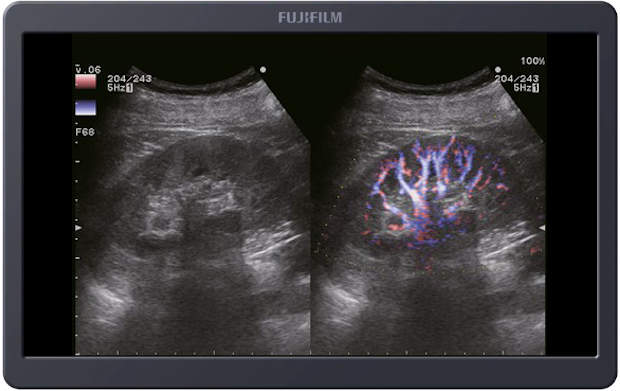

eFLOW - obrazowanie przepływu krwi o wysokiej rozdzielczości

eFLOW jest trybem obrazowania przepływu krwi o wysokiej rozdzielczości przestrzennej i czasowej. W eFLOW możliwe jest wyświetlanie informacji o przepływie krwi z wyższą czułością i rozdzielczością niż w przypadku klasycznych technik. Tryb ten umożliwia szczegółową obserwację drobnych naczyń krwionośnych, na przykład tych wewnątrz guza, które trudno byłoby wyświetlić osobno w trybach standardowych.

eFLOW ma zdolność rozdzielczą umożliwiającą osobne wyświetlenie tętnicy wątrobowej biegnącej obok żyły wrotnej. W konwencjonalnych metodach Color Doppler czy Power Doppler rozdzielczość przestrzenna jest niska. Powoduje to, że czasami z powodu artefaktu rozlewania się (tzw. blooming) naczynia krwionośne są wyświetlane jako grubsze niż w rzeczywistości.

Trudno byłoby odróżnić dwa cienkie naczynia krwionośne biegnące równolegle.

Dzięki poszerzeniu pasma przenoszenia nadajnik/odbiornik oraz zastosowaniu metody przetwarzania przeglądowego w eFLOW uzyskano nowy sposób obrazowania przepływu krwi. Charakteryzuje się on wysoką rozdzielczością przestrzenną i czasową. Co więcej, opisywany tryb obrazowania redukuje tłumienie sygnału przepływu krwi w każdym procesie przetwarzania danych. eFLOW usprawnia przetwarzanie w celu odróżnienia przepływu krwi od ruchu tkanki i umożliwia wyświetlanie drobnych naczyń krwionośnych wraz z kierunkiem przepływu, co jest przydatne klinicznie.